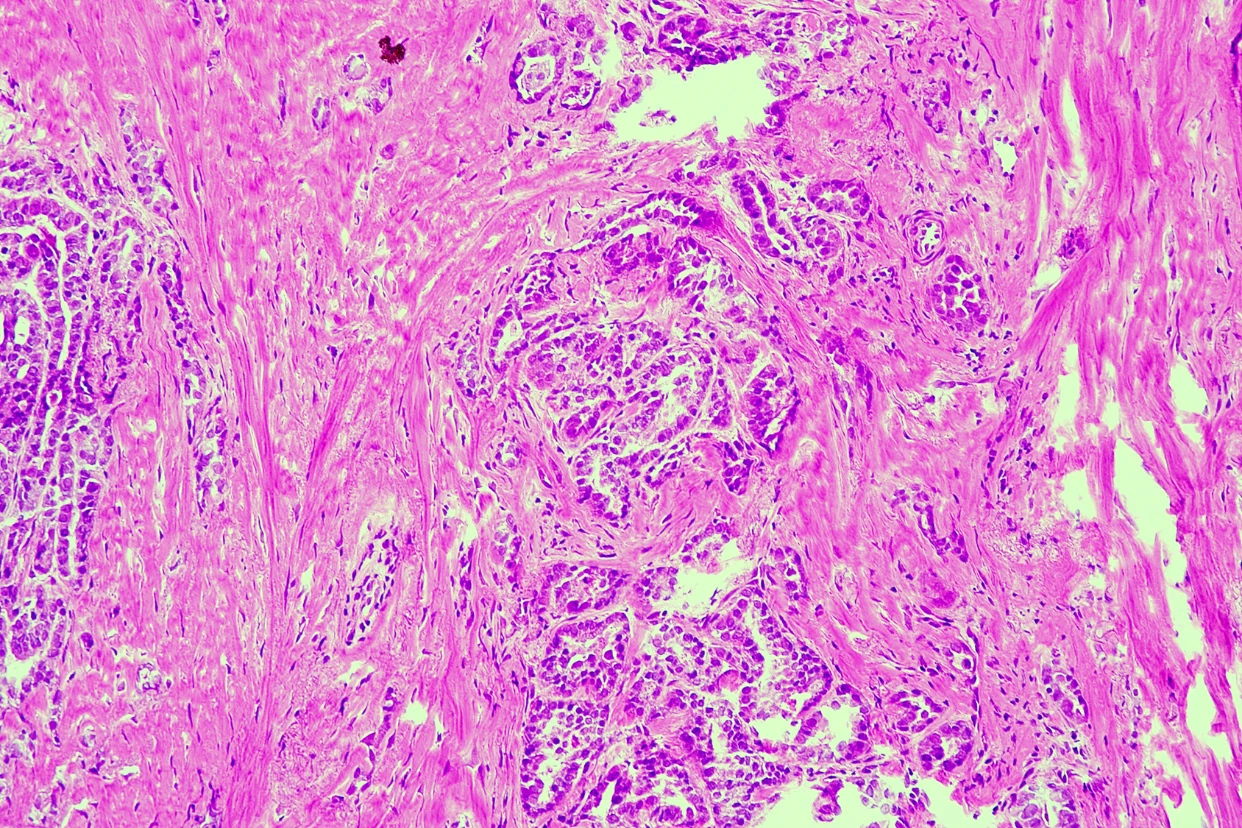

Mujer de 83 años con nódulo tiroideo izquierdo.

BAAF con diagnóstico de neoplasia folicular.

Para estudio transoperatorio se recibió hemitiroidectomia izquierda con un nódulo de 4.5 x 4.2 cm que ocupa el 95% del parénquima tiroideo.

1. ¿Qué hallazgos en el transoperatorio, considera crucial para el diagnóstico?

a) Patrón papilar

b) Áreas de necrosis

c) Infiltración del tumor en tejido peritiroideo

d) Respuestas b y c correctas

e) Áreas típicas de carcinoma papilar